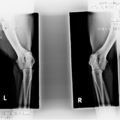

Beschrijving: Tessa verwacht tussen 31 januari en 8 februari haar eerste nestje pups, op de echo heeft de DA zeker 6 pups geteld. Tessa is Duitse/Mechelse/Hollandse herder kruising, ze is ED en HD getest maar niet officieel. de DA zei dat ze ED helemaal vrij is en ze net geen HDa heeft dus net HDb. Verder heeft ze de H474-D DNAtest gehad waarin ook de DM test zit en hier is ze overal vrij van. De dekreu is een Duitse herder langstokhaar genaamd Turbo. turbo's ouders hebben beide wel een stamboom, maar Turbo zelf heeft er geen. het is een erg lieve en sociale reu van 2jaar oud en kan goed mat alle dieren en kinderen. hij is HD en ED vrij, maar heeft verder NOG geen andere testen gehad.

de ouders zijn op ED en HD getest, de vader is ED en HD vrij en de moeder EDvrij en heeft HDb. verder heeft Tessa de H474-D DNAtest gehad en was op alle punten helemaal vrij, waaronder de DM test.